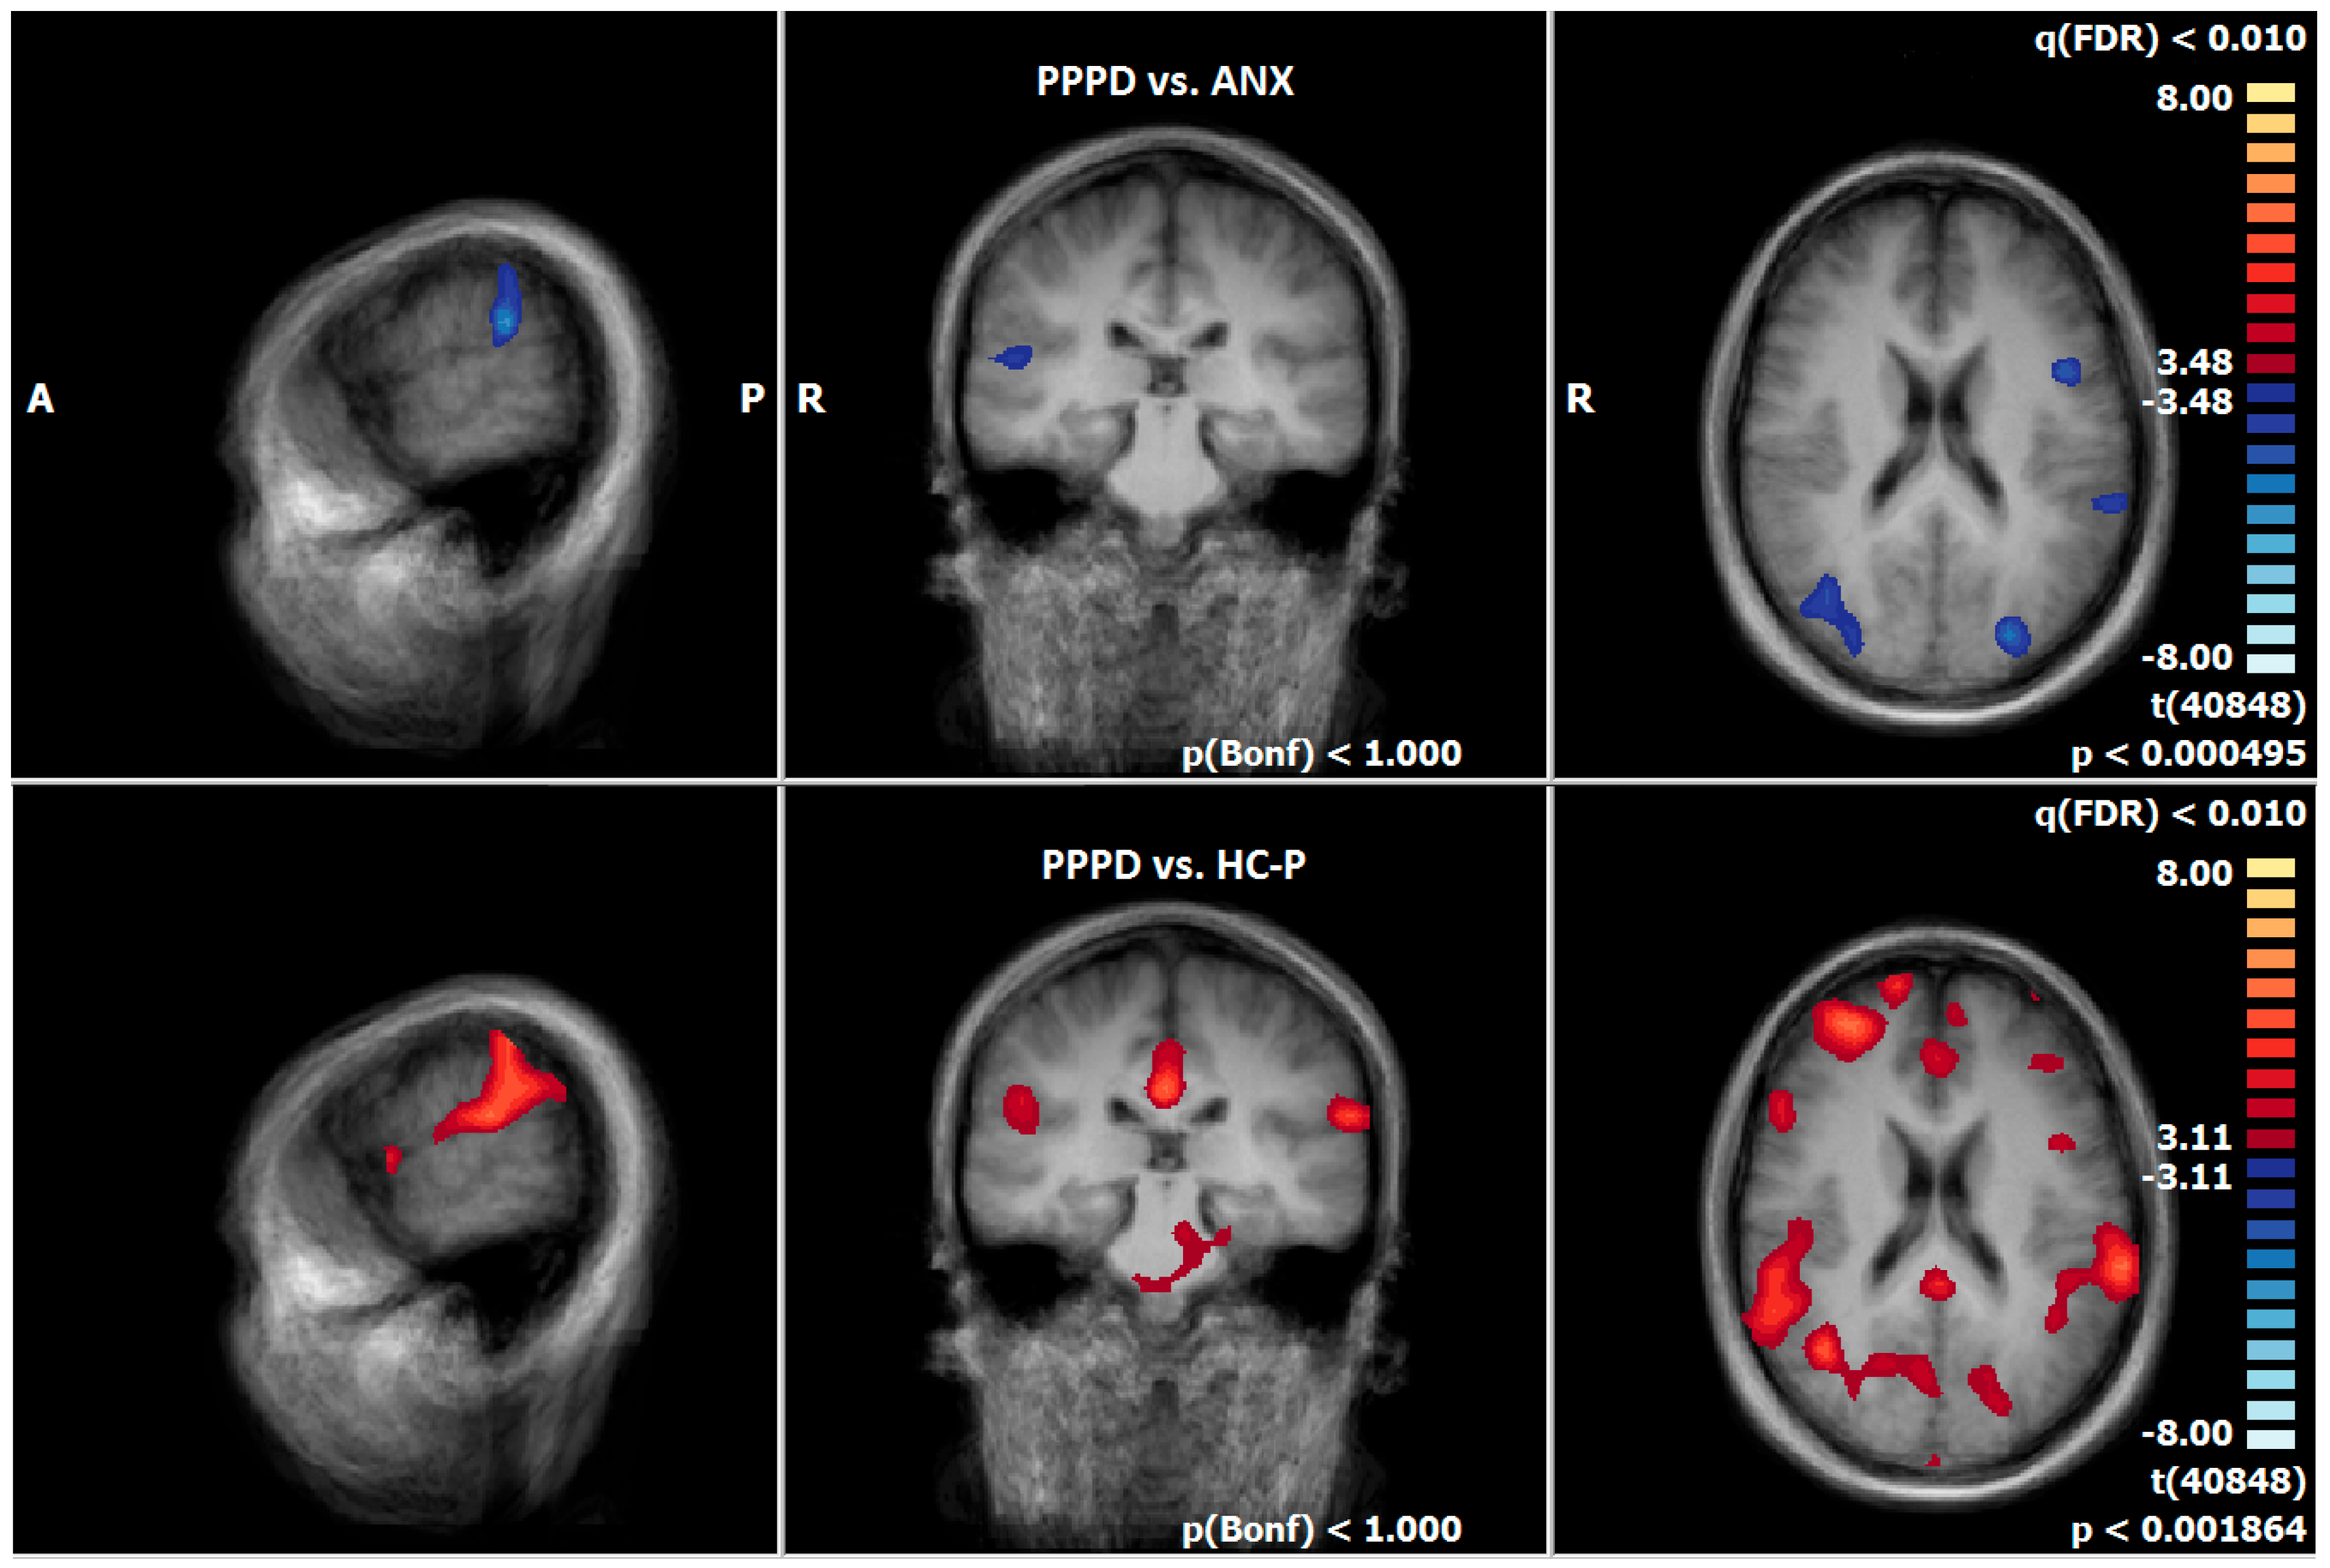

3.7. Post-Treatment Comparison of Neuronal Responses Between PPPD and ANX

3.8. Post-Treatment Comparison of Neuronal Responses Between PPPD and HC-P